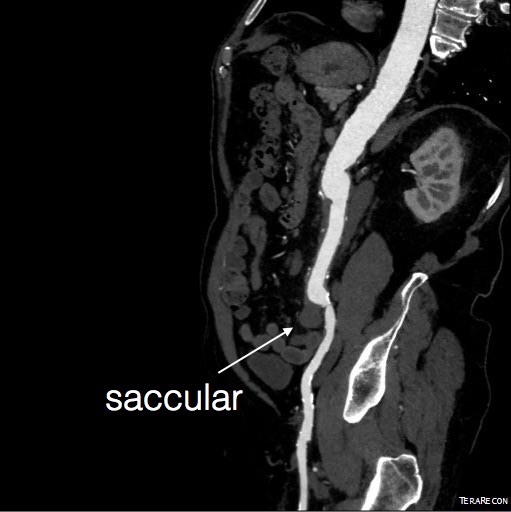

Compared to my other parallel graft case treating a metachronous saccular common iliac aneurysm years after an EVAR with a Gore endograft (link), which by table calculation, resulted in 8% oversize in calculated areas, this particular technique with a large AFX graft and an appropriately sized Viabahn seemed to work well the setting of a previously placed AFX graft. It allows one to avoid hypogastric occlusion.